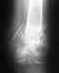

Покажите снимок, хотя бы последний. Можно здесь. Можно приехать на Московскую, 12, с понедельника по четверг включительно, с утра.